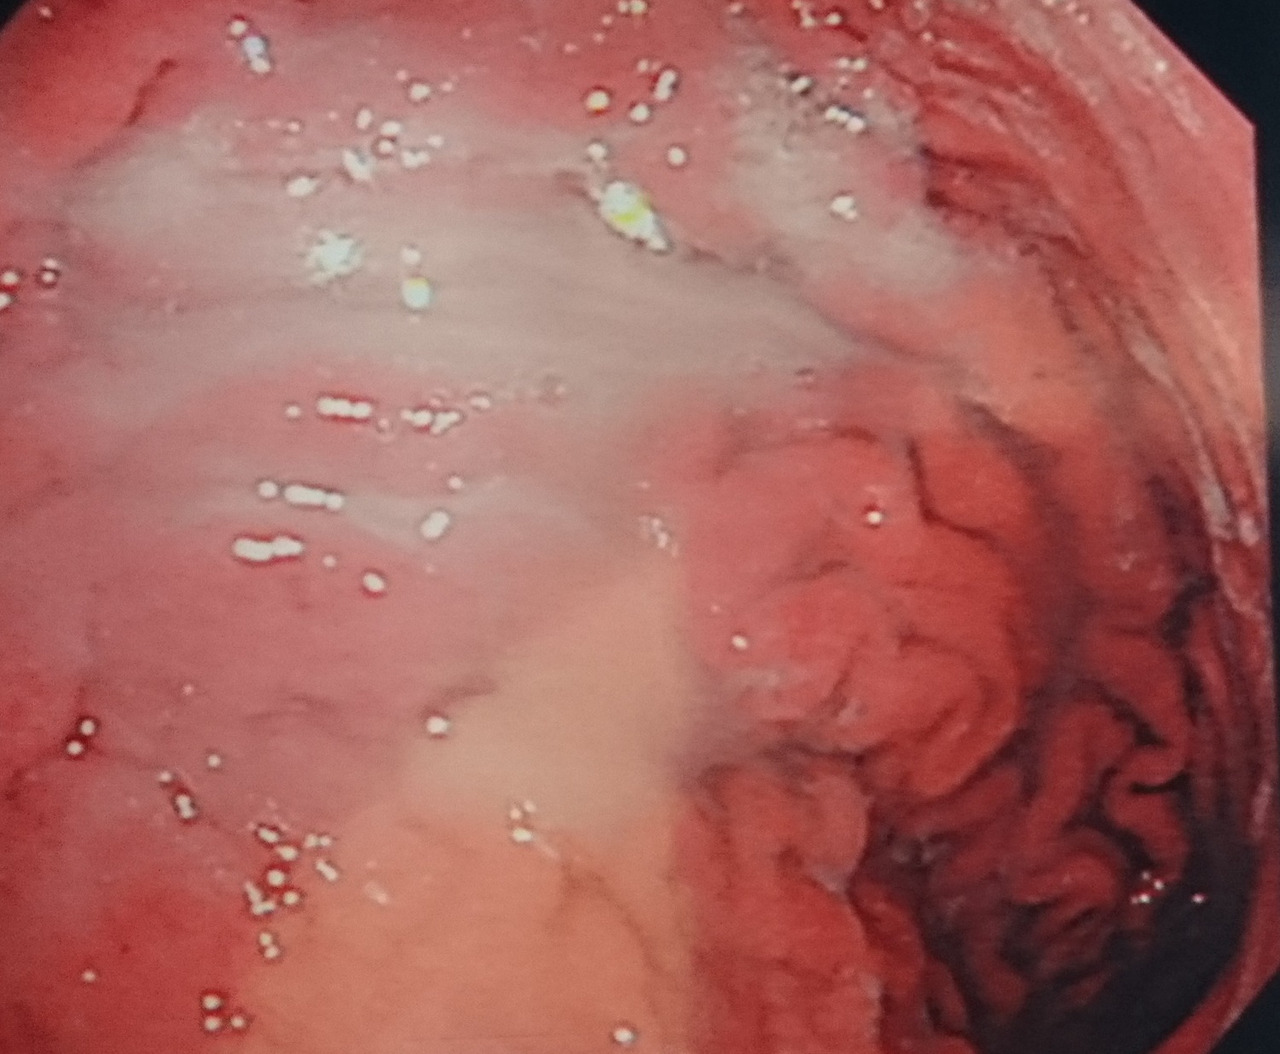

- 미란, 궤양, 백태성 변화 등이 관찰되는 경우

- 위점막의 얇아짐, 창백함

- 장점막 형태가 나타나는 변화

미란·궤양의 변성 여부 평가

겉으로 보기에는 단순 궤양이지만 실제로는 악성 궤양의 형태인 경우가 있어, 의심 부위에서는 조직검사가 필수입니다. 특히 경계가 불규칙하거나 두꺼워 보이는 궤양은 초기 암일 가능성을 배제하기 위해 반드시 세포 검사가 이루어져야 합니다.

육안 소견만으로는 정상 점막과 거의 구별이 안 되는 경우가 많아,

- 색조의 미세한 차이

- 얕은 함몰

- 표면 패턴 변화

등을 근거로 조직검사를 시행합니다. 이 단계에서의 조직검사는 생명 예후와 직결되는 진단 과정입니다.